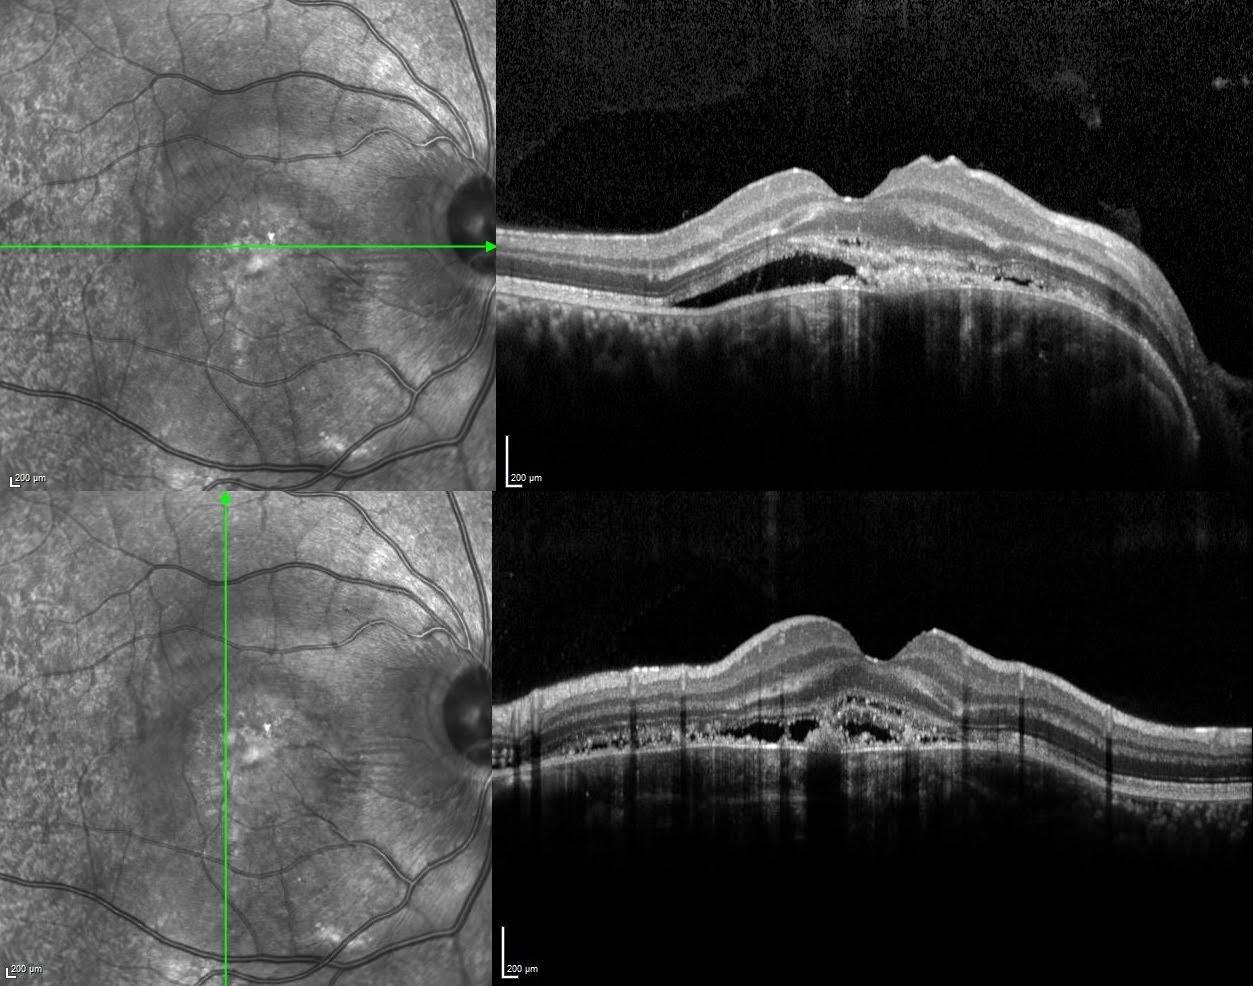

The OCT scan revealed a hyperreflective, plate-like choroidal lesion located beneath the RPE, consistent with choroidal osteoma. There is dense posterior shadowing due to the calcified mass, obscuring deeper structures. Overlying the lesion, the outer retinal layers exhibit thinning and disruption of the ellipsoid zone. A dome-shaped elevation of the RPE with underlying subretinal hyperreflective material suggests the presence of choroidal neovascularization, supported by intraretinal fluid and architectural distortion.

The OCTA image reveals flow voids in the area corresponding to the calcified portions of the choroidal osteoma, seen as hyporeflective regions due to signal attenuation. In the central macular region, irregular vascular networks are observed, suggesting secondary choroidal neovascularization (CNV). This HD-OCTA scan reveals a well-circumscribed, dense neovascular network within the outer retina or choriocapillaris layer, consistent with choroidal neovascularization (CNV) secondary to choroidal osteoma. The en face angiogram clearly shows a tangled vascular complex with high flow signal. Structural OCT demonstrates RPE elevation, subretinal hyperreflective material, and intraretinal fluid—all indicative of active CNV.